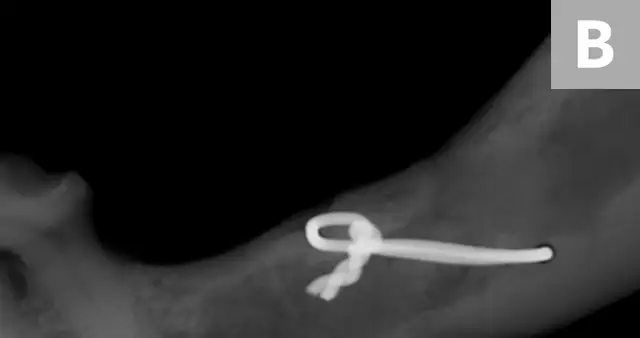

The patient was presented 7 weeks later for a recheck oral examination under general anesthesia (performed in the same manner as previously). Dental radiographs demonstrated healing of the fractures (Figure 4). The interfragmentary wires were removed via an intraoral approach, and postoperative intraoral radiographs were obtained to confirm adequate healing (Figure 5). The patient recovered uneventfully.

Postoperative intraoral dental radiographs of the right (A) and left (B) mandible following reduction and fixation with a single intraosseous wire on each side.